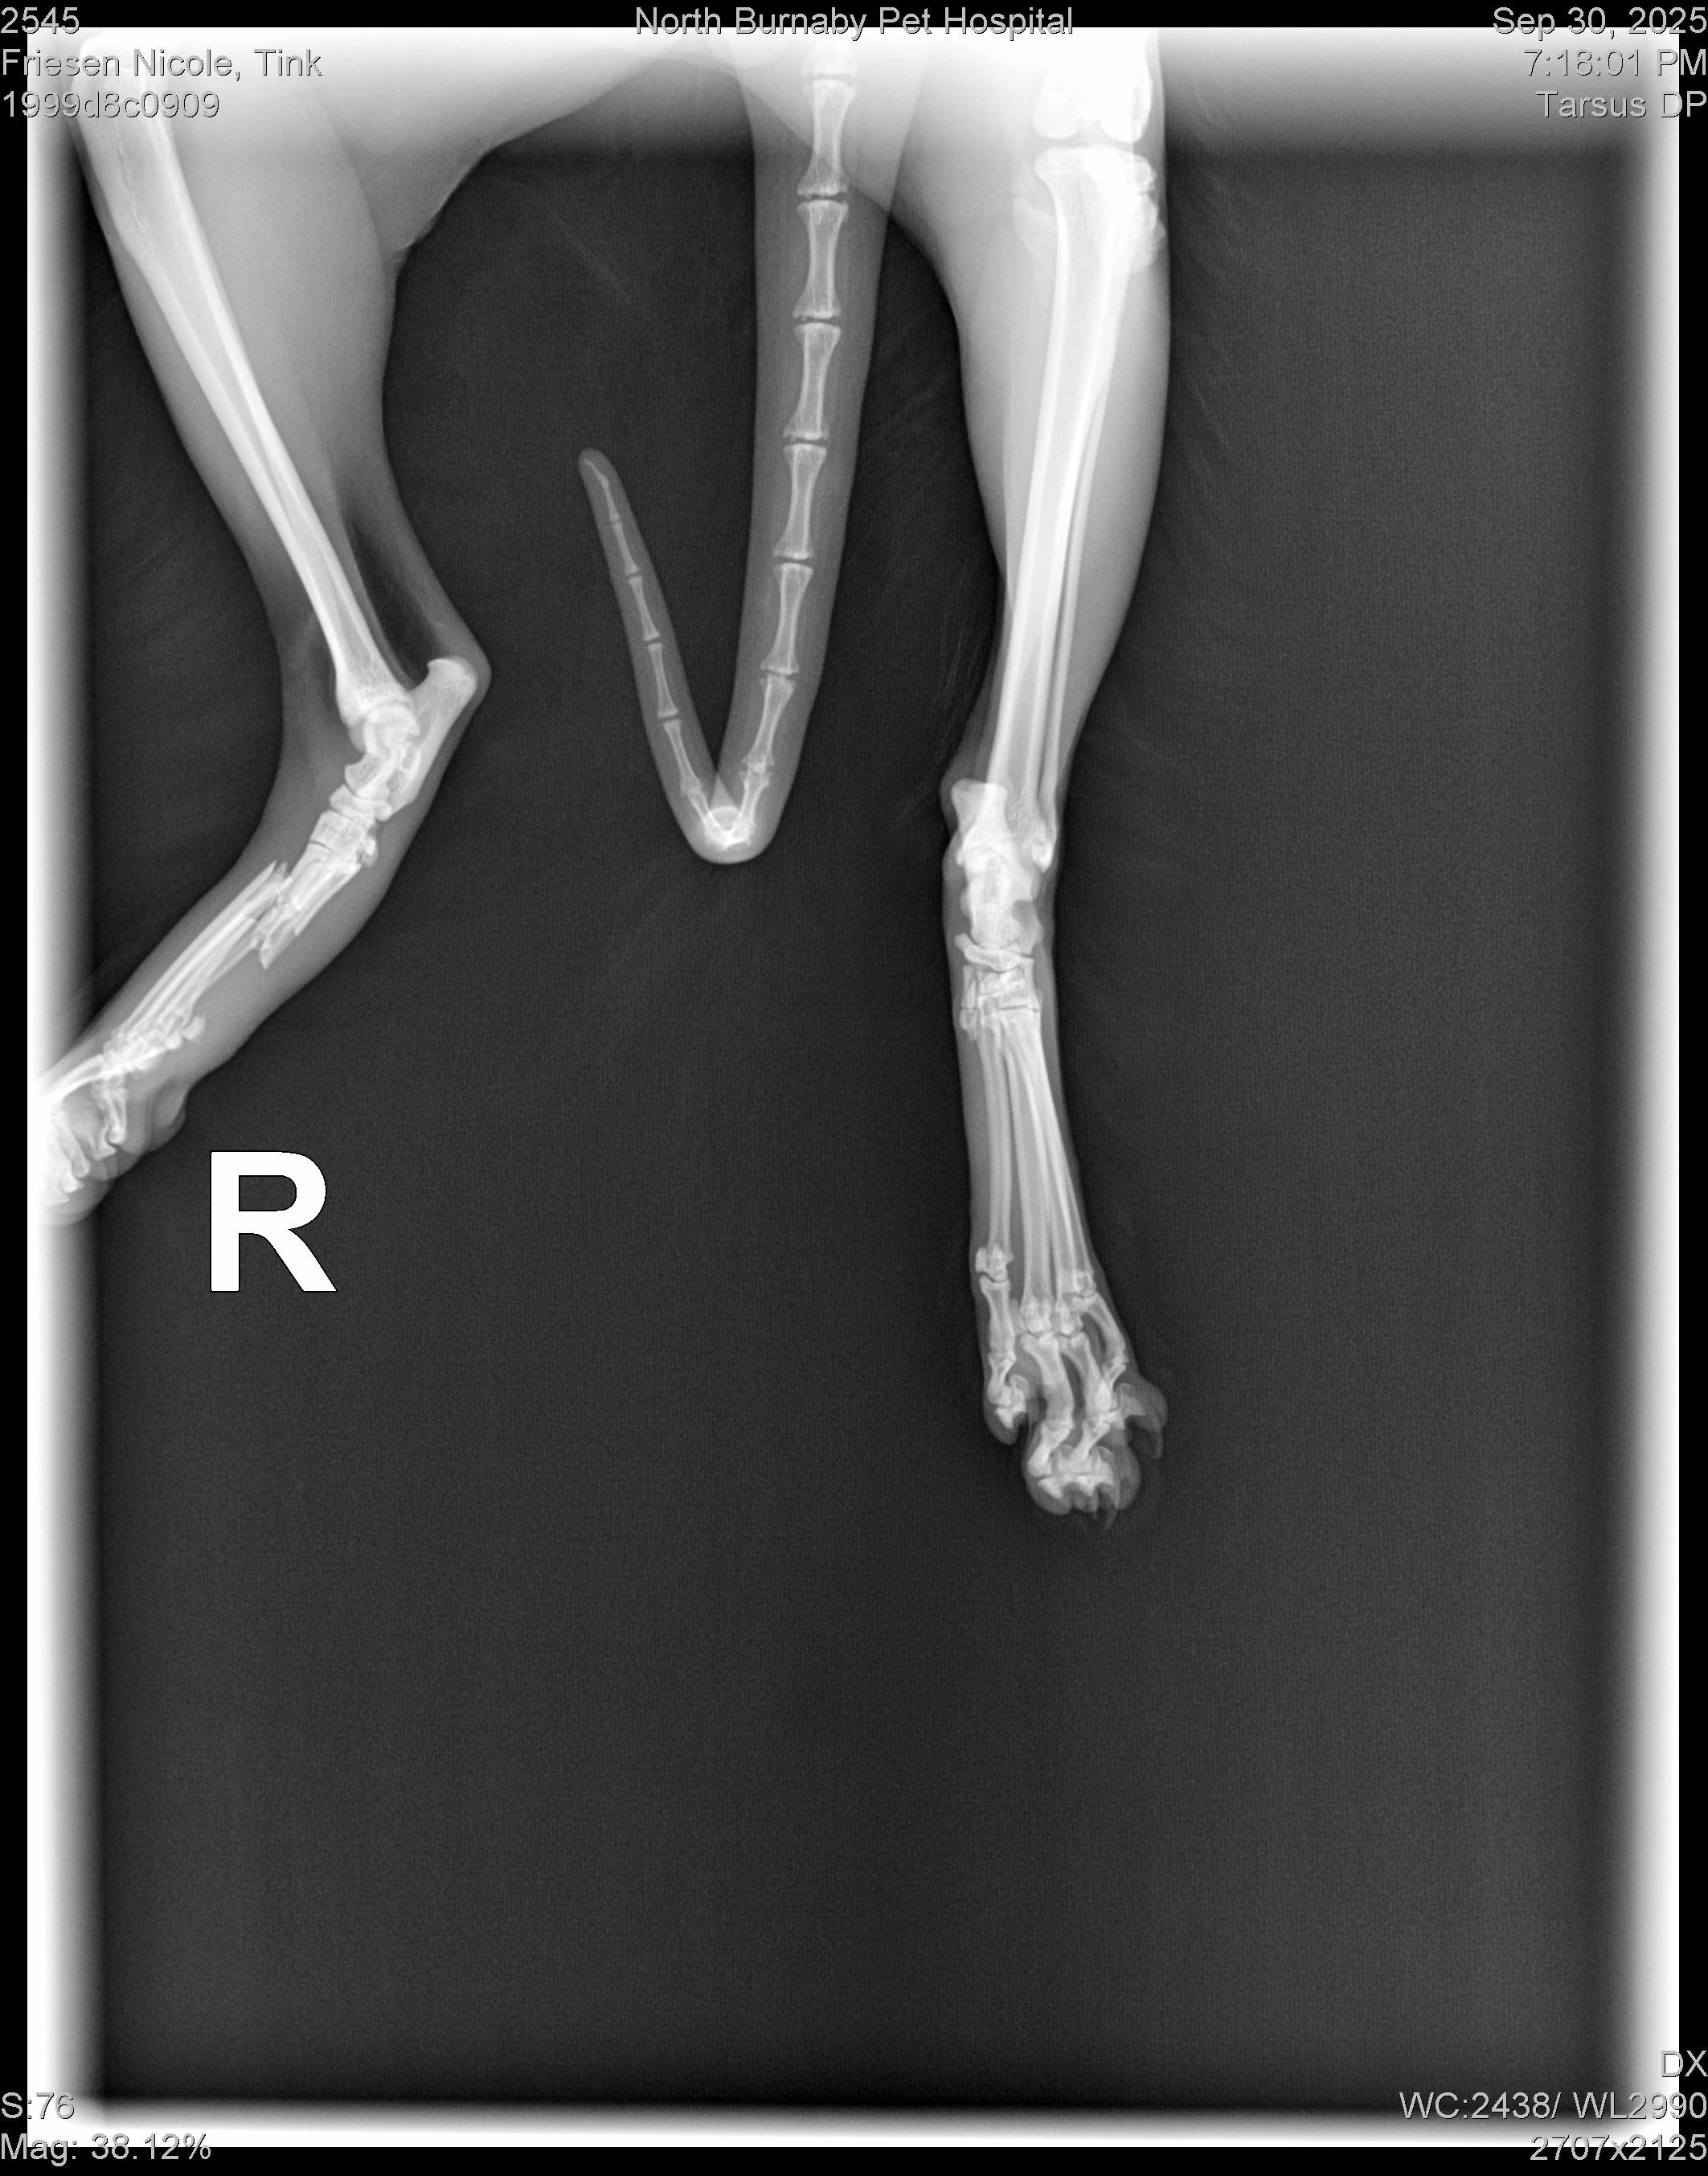

Early this week, my treasured cat Tink broke his foot. He is going into orthopaedic surgery as I write this post. Without this operation, he won’t be able to heal properly, walk normally, or live without constant pain; a fate for him that I cannot accept and will do anything to change. Luckily, his vet is an absolute angel—a “care for critters now, worry about money tomorrow” kind of doctor. The clinic has been incredibly patient with me as I navigate this situation.

(Shout out to North Burnaby Pet Hospital for prioritizing pets over profits—the quote I received for Tink’s care from another clinic was $8-10k)

The surgery taking place today is $4,000, and afterwards he’ll need two months of weekly follow-up vet visits to change his bandages, monitor his healing and ensure that he has many happy, healthy and mobile years ahead of him. Altogether, the cost of care will be over $5,000.